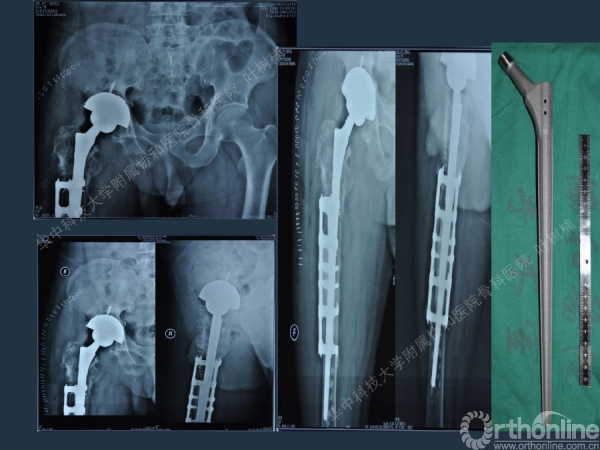

股骨侧翻修